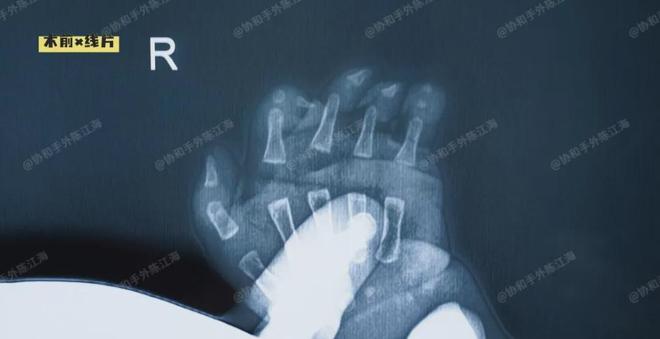

这个小宝宝是波兰综合征,右手不仅手指短,还连在一起(短指并指),同时胸肌发育也不好。

在孩子6个月的时候,我们采用人工真皮诱导免植皮技术,一次手术分开了孩子的并指。

手术按计划进行,我们成功地一次分离了孩子右手的3个指蹼,并采用人工真皮覆盖创面。手术的顺利完成只是第一步,接下来的术后护理至关重要。